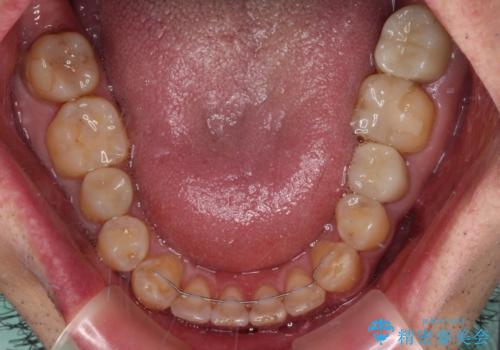

- 虫歯が多く、セラミッククラウンにより虫歯治療を行っている途中で矯正治療をしたいとのことで来院された患者様です。

上顎前歯が舌側に転位しており、なるべく早く楽に矯正したいとのことで、ワイヤー矯正を行うこととしました。

虫歯治療途中の歯は仮歯が装着されていたため、そのまま矯正治療を行い、矯正後に補綴治療を行うこととしました。